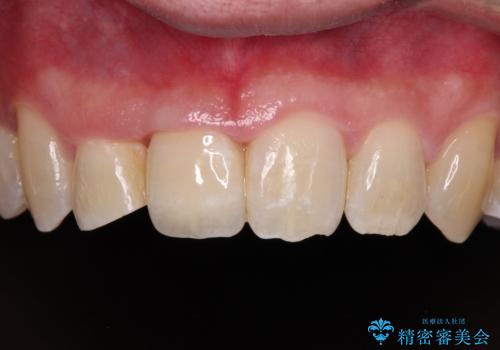

矯正治療後にはオーダーメイドタイプのオールセラミッククラウンを装着し、自然な口元に仕上がりました。